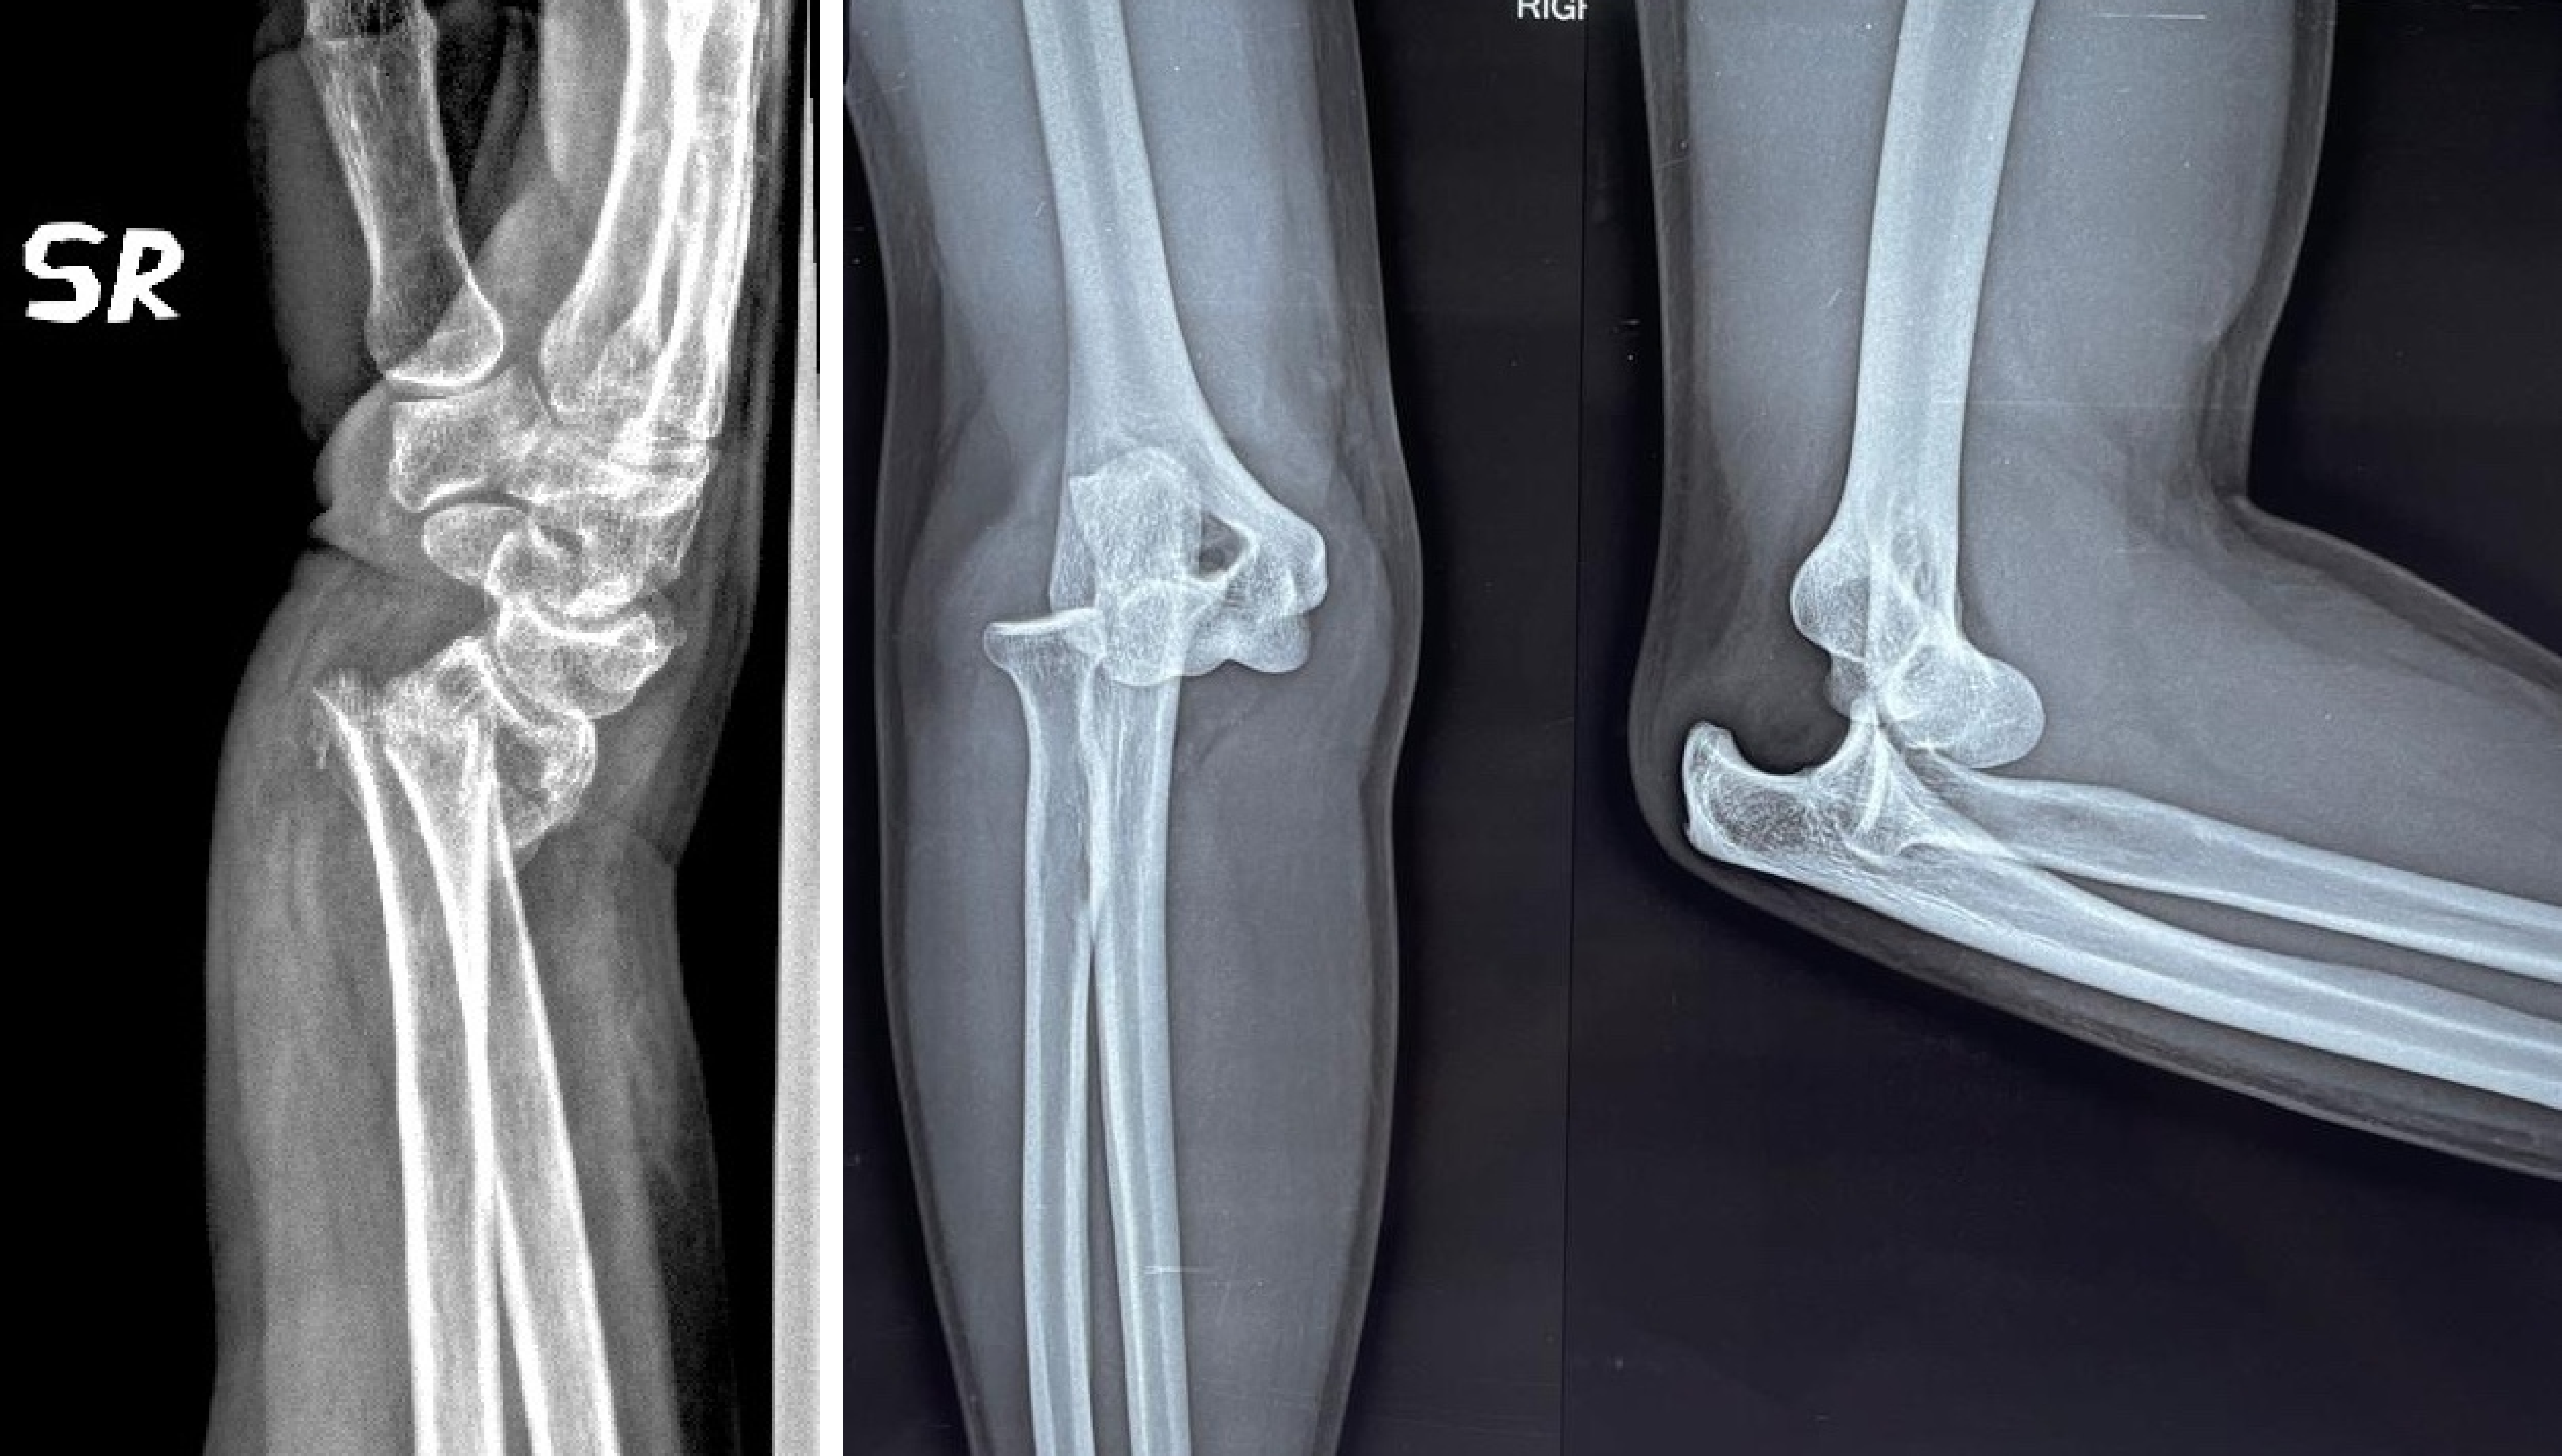

X-rays: To detect fractures or dislocations

Fractures: Broken bones in fingers, metacarpals, or wrist

Dislocations: Bones forced out of their normal position